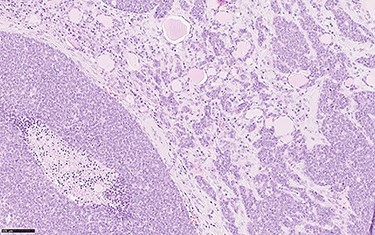

Histological section showing solid sheets, with comedo necrosis, and nests of neoplastic cells infiltrating thyroidal parenchyma (haemotoxylin and eosin, o.m. ×20).

In December 2018 a total thyroidectomy was conducted, with finding of extensive infiltration of perithyroidal soft tissue, incorporation of the left inferior laryngeal nerve, infiltration of the trachea, without infiltration of the oesophagus (Fig. 3). The left thyroid lobe resulted subverted by neoplastic proliferation with necrosis, perineural and vascular invasion (PNVI), infiltration of perithyroidal soft tissue, lymph node and surgical margins (Fig. 4). Immunophenotype: smooth muscle actin (SMA)+, CD117+, CK7+, TTF1−, PAX8−, Thyroglobulin−, NapsinA−, CD45−, CK20−, S100−, GFAP−, p63−, GATA3− (Fig. 5). After comparison with the previous examination, the immunomorphological patterns were similar, and the possibility of a primary ACC of thyroid was also considered, but since preoperative radiological and nuclear imaging examination excluded thyroid involvement, the most likely hypothesis was for the thyroid lesion to be a metastatic localization of a primary ACC of the lung.